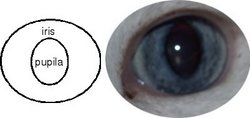

El iris, junto al cuerpo ciliar, forma la úvea anterior. Su misión es regular la cantidad de luz que tiene que entrar en el ojo. Separa a la cámara anterior de la posterior, por lo que está rodeado de humor acuoso. La pupila es el "agujero" que deja abierto el iris. |

El iris tiene unas fibras radiales, dilatadoras, midriásicas. |

También tiene unas fibras concéntricas, constrictoras, mióticas. |